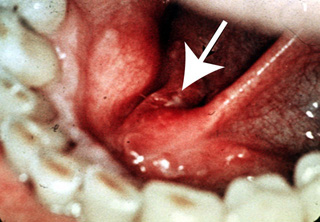

Cáncer pequeño

La primera imagen muestra una lesión roja pequeña, granular

o atercipelada (ver flecha) en el suelo de la boca adyacente al conducto de Wharton. Esto es totalmente

asintomático y solo se percive como un ligero espesamiento de la

mucosa. El paciente puede curarse si la enfermedad se descubre en esta fase; sin embargo,

este tipo de lesión puede no ser detectada en el examen oral y desde

luego continúa creciendo. (Photograph courtesy of Dr. S. Rovin.) |